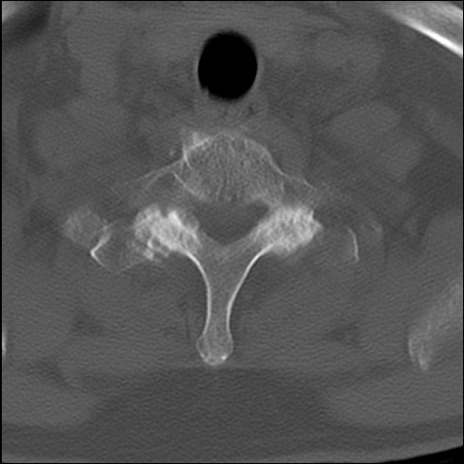

頚椎CT

冠状断像